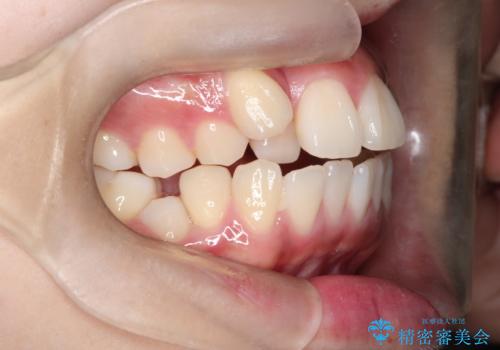

【ワイヤー矯正】オープンバイトを治したい

- 4番の歯を4本抜歯をし、上顎にマイクロインプラントを2本埋入し、遠心移動を行いました。

主訴のオープンバイトは改善し、抜歯をしたことで前歯が下がり綺麗になりました。抜歯矯正でしたが1年2か月という短い期間で終了しました。